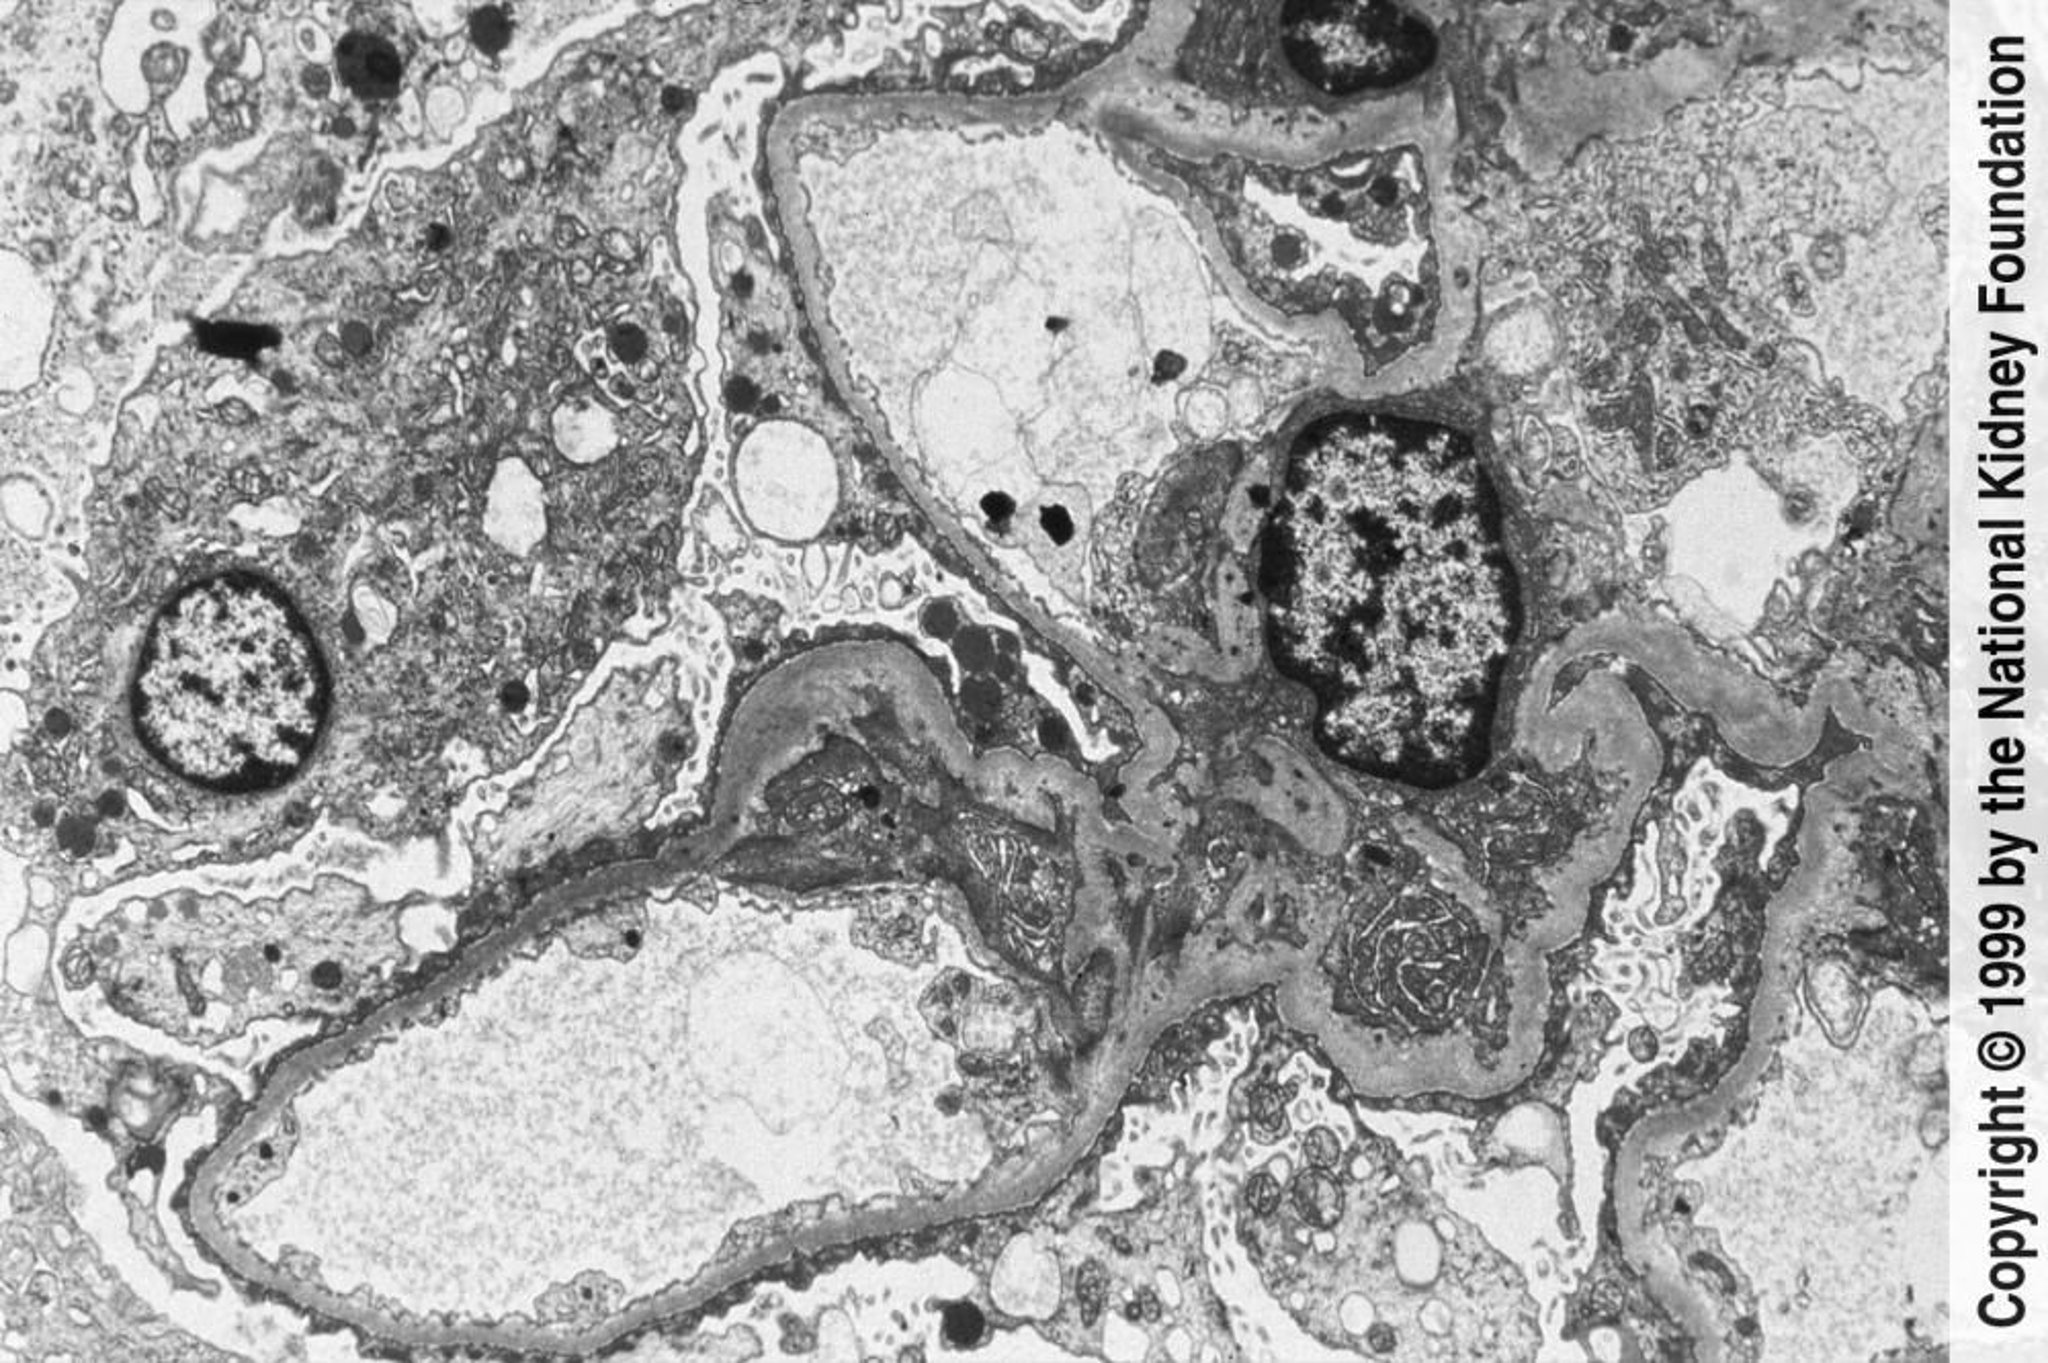

Glomerulosclerosis focal y segmentaria (pedicelos redondeados y efacelados)

Se pueden identificar pedicelos con aplanamiento extenso y erosión microscopia electrónica de transmisión (×3000).

Image provided by Agnes Fogo, MD, and the American Journal of Kidney Diseases' Atlas of Renal Pathology (véase www.ajkd.org).